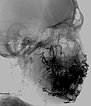

DSA, anterior-posteriore Ansicht, nach Anspritzen der rechten A. carotis communis. Auch aus der kontralateralen rechten A. carotis externa und A. facialis rechts wird der Nidus der AVM an der linken Wange gespeist.